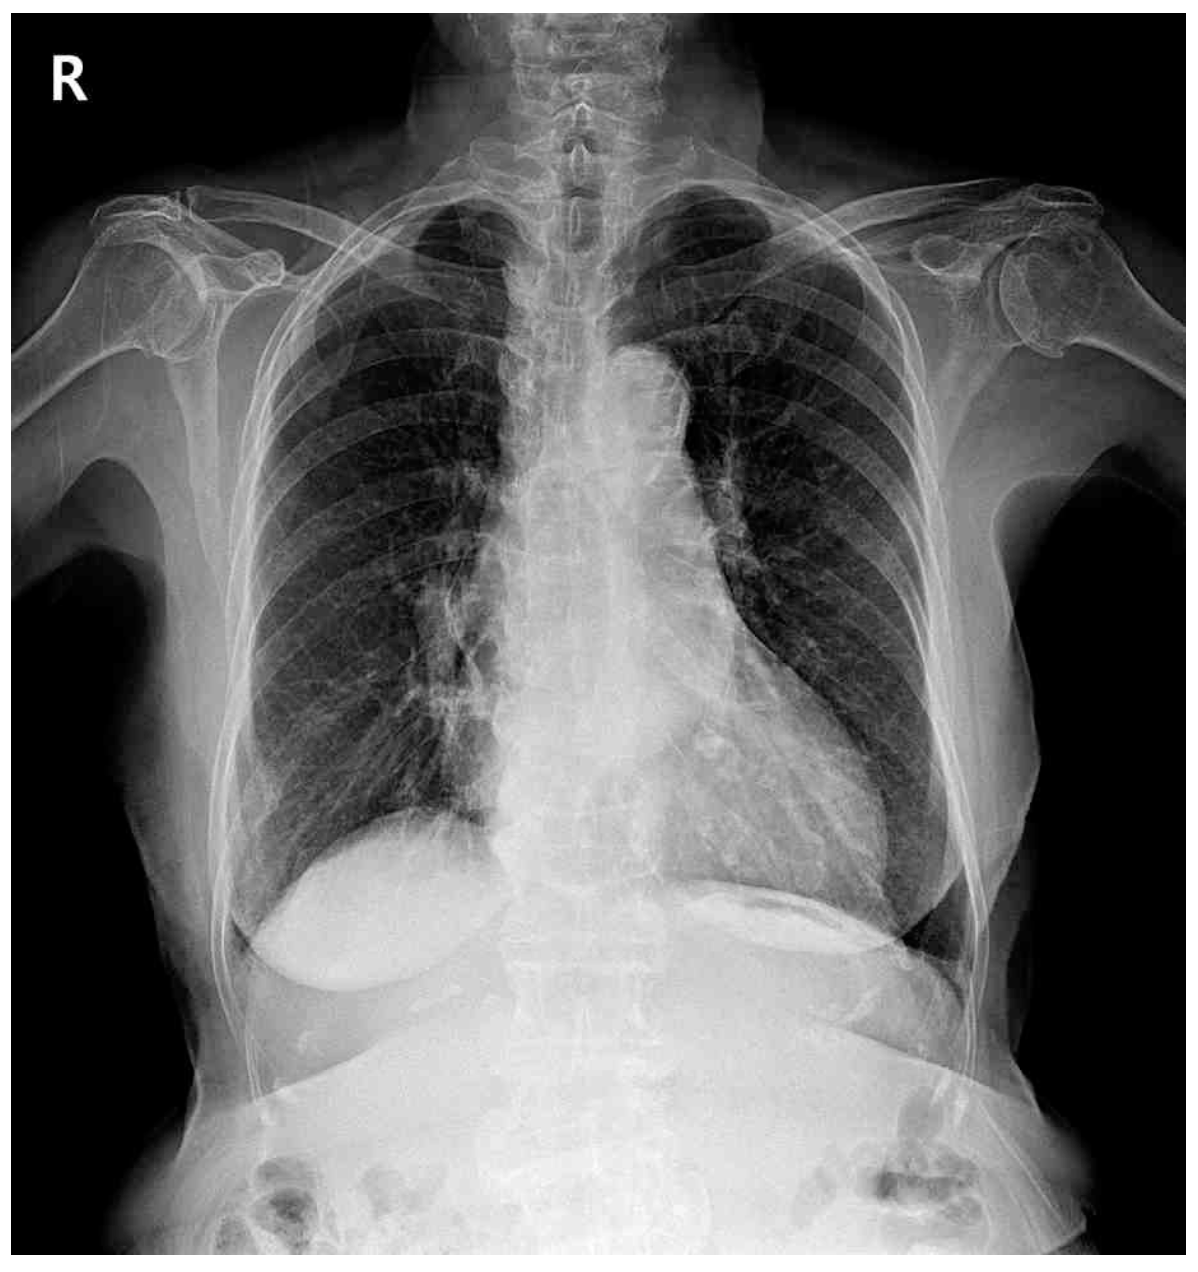

70세 여자가 직장암으로 저위전방절제를 받고 입원 중이다. 수술 후 2일째 가슴이 답답하다고 한다. 혈압 90/65 mmHg, 맥박 105/분, 호흡 28회/분, 체온 36.8°C이다. 양측 폐의 호흡음은 정상이며, 배는 수술부위 통증 외에 특별한 이상은 없다. 검사 결과는 다음과 같다. 가슴 X선사진과 가슴 컴퓨터단층촬영 사진이다. 진단은?

CXR: No remarkable findings

• 무기폐: 발열과 함께 CXR상 무기폐로 의심되는 소견이 확인되어야 하나 해당 증례에서는 확인할 수 없다.

• 가슴막삼출: 삼출 부위 호흡음 감소 및 CXR상 CPA blunting이 관찰된다.

• 대동맥박리: 특징적인 찢어지는 듯한 극심한 흉통과 mediastinal widening이 CXR에서 확인된다.